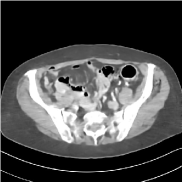

Refer to caption FBPRMSE = 194.09 HURefer to caption FBPRMSE = 194.09 HURefer to caption PWLS-ULTRARMSE = 43.40 HURefer to caption PWLS-ULTRARMSE = 43.40 HU

Refer to caption FBPConvNetRMSE = 34.24 HURefer to caption FBPConvNetRMSE = 34.24 HURefer to caption SUPER-FCN-DataTermRMSE = 31.21 HURefer to caption SUPER-FCN-DataTermRMSE = 31.21 HU

Refer to caption SUPER-FCN-ULTRARMSE = 28.82 HURefer to caption SUPER-FCN-ULTRARMSE = 28.82 HURefer to caption ReferenceRefer to caption Reference

Figure 5: Reconstructed images of slice 150 of patient L192 using of FBP, PWLS-ULTRA, FBPConvNet, SUPER-FCN-DataTerm, and SUPER-FCN-ULTRA, respectively, shown along with the reference.

Fig. 5 shows reconstructions using FBPConvNet, SUPER-FCN-DataTerm (i.e., β=μ=0𝛽𝜇0\beta=\mu=0), PWLS-ULTRA, and SUPER-FCN-ULTRA, respectively. For SUPER-FCN-DataTerm, when optimizing the data-fidelity term, we start with the deep network’s output and ran 5 iterations for the data-fidelity term to avoid overfitting to the analytical FBP images. In Fig. 5, obviously, FBPConvNet significantly suppresses noise and artifacts compared to PWLS-ULTRA, but it also over-smooths many details (e.g., features in the zoom-in box) in the reconstruction. SUPER-FCN-DataTerm, by enforcing data consistency, helps reduce overfitting issues and reconstructs image details and tissue boundaries better compared to the standalone FBPConvNet. Our SUPER-FCN-ULTRA method, however, exploits richer prior information (via the union of learned sparsifying transforms) and explicit network regularizer and outperforms the SUPER-FCN-DataTerm approach. Additional such comparisons for other selected test slices are included in the supplement (Fig. 15).